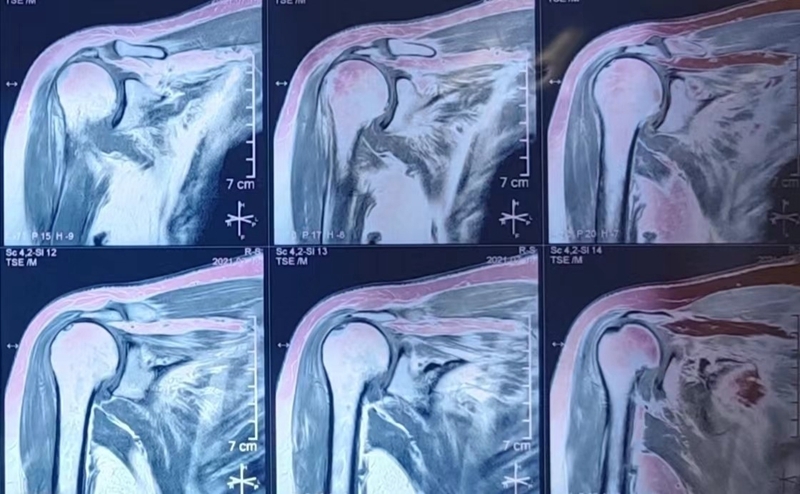

65岁女性,无明显诱因出现右肩疼痛、活动受限1年,外伤后加重2个月入院。术前右肩典型“假性瘫痪”,功能状态如图所示:

图GIF1~4

术前影像学检查示肱骨头向上移位,关节盂、肩峰和肱骨头退行性改变,典型肩袖撕裂性骨关节病(CTA)改变。